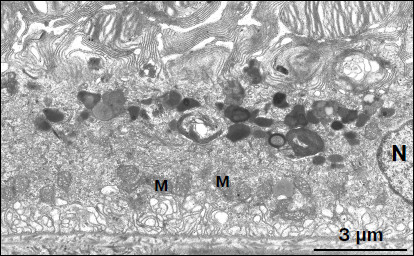

Figure 6

Fig. 6. Region of pigment epithelium of 11-month-old OXYS rat treated with SkQ1 drops (250 nM). The layer of electron-dense cytoplasmic inclusions is clearly seen. N, cell nucleus; M, mitochondria.

Electron microscopy showed that after treatment with SkQ1 drops, the ultrastructure of pigment epithelium cells changed significantly. An aggregate of numerous electron-dense structures looking as a strongly developed continuous layer, passing through all pigment epithelium cells, was revealed in apical cytoplasm of the latter (Fig. 6). It is also necessary to note that in separate regions of the pigment epithelium we detected the appearance of a second layer of cells with the strongly developed system of mitochondrial reticulum (Fig. 7). In this case, electron-dense structures were localized mainly in the upper layer of pigment epithelium cells. Our results show that, like in Wistar rats, morphology of these cytoplasmic inclusions is very diverse. They contain lipofuscin granules, but mainly this layer contains different structures. They are oval electron-dense structures filled by an electron-dense substance. We managed to find that separate such structures are mitochondria partially filled by electron-dense material. Besides, organelles of unusual ultrastructure are present in cytoplasmic inclusions. They are of round or spherical shape, surrounded by a single-layer membrane, its internal space filled by granulated matrix and tightly adjacent concentric membrane layers (Fig. 8). The origin and functional significance of these structures are still unknown.